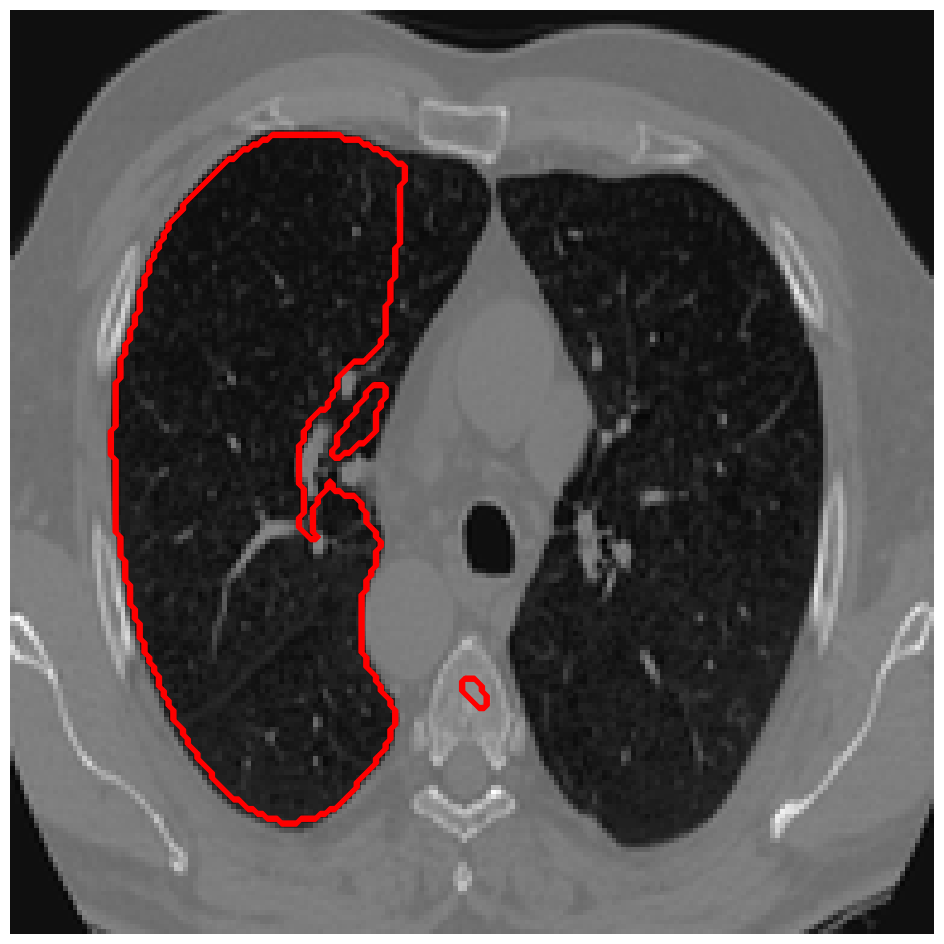

Figure 5: A sample result on the Liver data. We display the input image with the user input \mathcal{M}, the ground truth (GT) and results from the four methods. Moreover, we show comparisons with the model (4) solved in a variational framework with both Total Variation (TV) and Euler Elastica as explicit regularisation, as well as a comparison with the model solved in a Deep Image Prior framework.

Similarly we show some results in Figures 5 and 6 from the LiTS dataset of all the methods. Quantitative results of the 272727 images can be found in 2. Clearly for both datasets, M3 and M4 using the proposed ideas outperform M1 and M2, as well as methods using explicit regularisation (TV and Elastica), and the original DIP method.